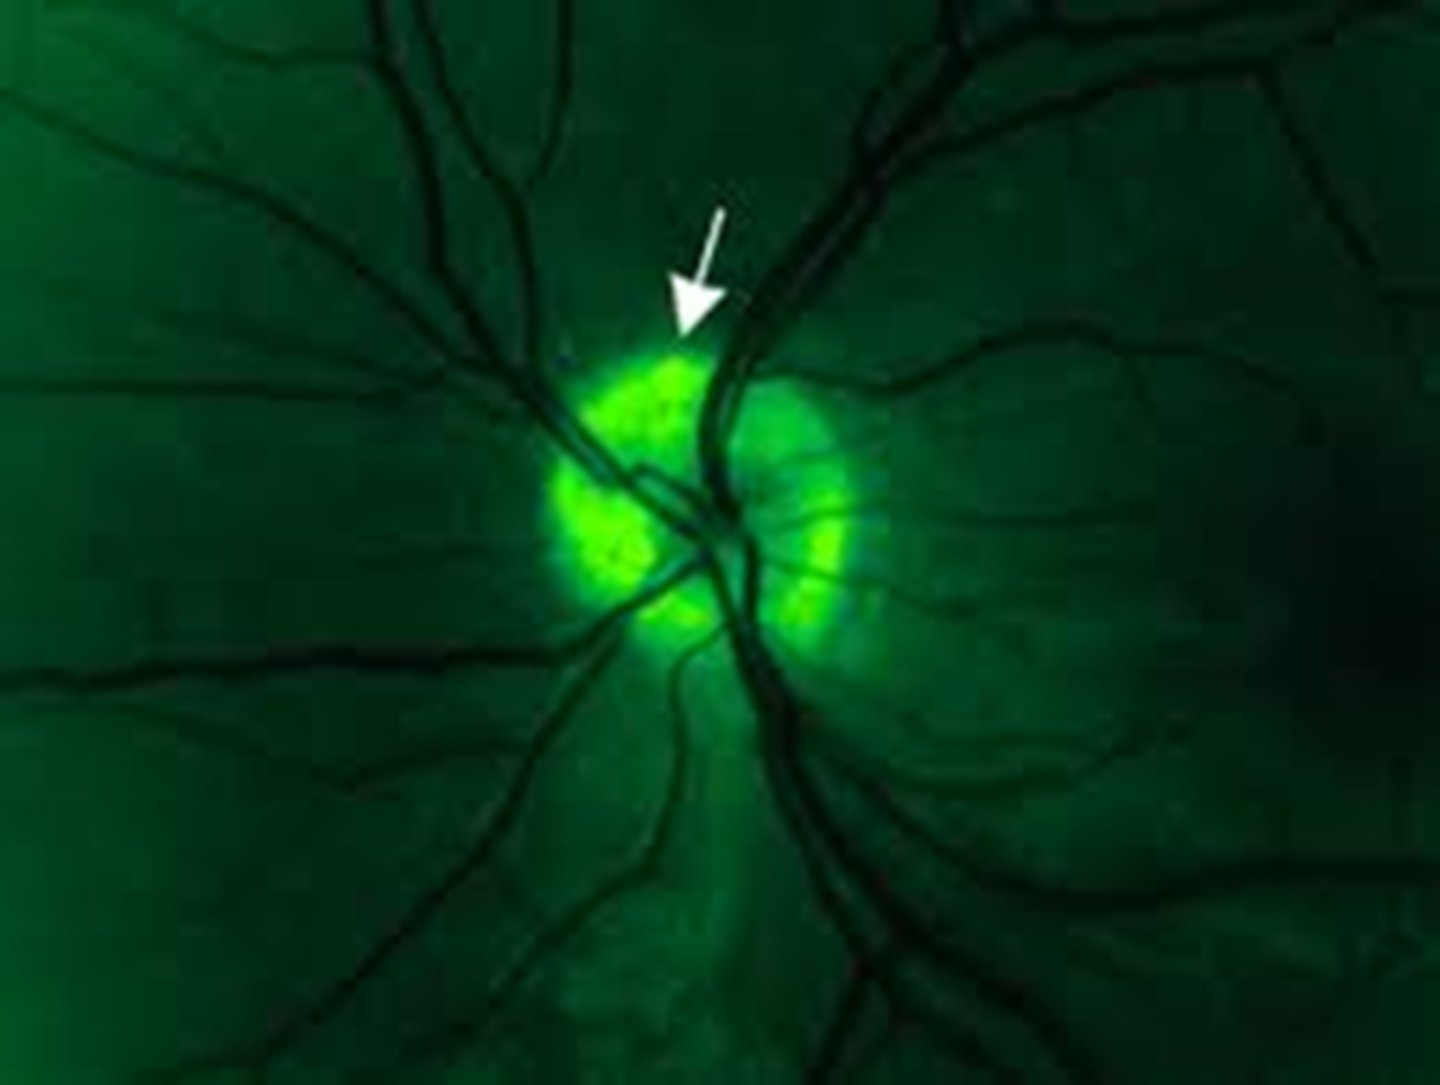

How do disc drusen appear on FAF?

hyperAF drusen within the hypoAF nerve head

How do surface drusen appear on early IVFA?

blockage

How do surface drusen appear on late IVFA?

nodular staining

How do buried drusen appear on early IVFA?

no staining or nodular staining

How do buried drusen appear on late IVFA?

late peripapillary staining (noduler, circumferential)